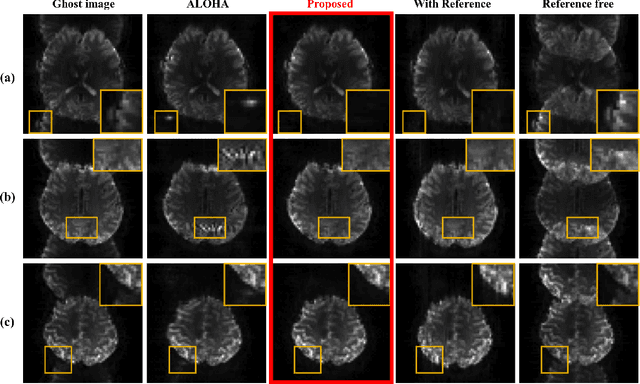

Abstract:Nyquist ghost artifacts in EPI images are originated from phase mismatch between the even and odd echoes. However, conventional correction methods using reference scans often produce erroneous results especially in high-field MRI due to the non-linear and time-varying local magnetic field changes. Recently, it was shown that the problem of ghost correction can be transformed into k-space data interpolation problem that can be solved using the annihilating filter-based low-rank Hankel structured matrix completion approach (ALOHA). Another recent discovery has shown that the deep convolutional neural network is closely related to the data-driven Hankel matrix decomposition. By synergistically combining these findings, here we propose a k-space deep learning approach that immediately corrects the k-space phase mismatch without a reference scan. Reconstruction results using 7T in vivo data showed that the proposed reference-free k-space deep learning approach for EPI ghost correction significantly improves the image quality compared to the existing methods, and the computing time is several orders of magnitude faster.